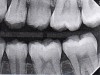

Fig 6. Three thin soft dental picks were used simultaneously for SDF proximal surface saturations in a teenaged patient (Fig 3). After 60 seconds, the treated regions were covered with 5% fluoride varnish (Fig 4). A comparison can be seen of pre-SDF-treatment bitewing films (Fig 5) and 8-month post-SDF bitewing films (Fig 6) for the patient shown in Fig 3 and Fig 4. Radiolucencies were similar or improved, except for contact of maxillary first and second molars.

Fig 3. Three thin soft dental picks were used simultaneously for SDF proximal surface saturations in a teenaged patient (Fig 3). After 60 seconds, the treated regions were covered with 5% fluoride varnish (Fig 4). A comparison can be seen of pre-SDF-treatment bitewing films (Fig 5) and 8-month post-SDF bitewing films (Fig 6) for the patient shown in Fig 3 and Fig 4. Radiolucencies were similar or improved, except for contact of maxillary first and second molars.

Interproximal insertion of SDF is demonstrated in different patients in Figure 3 through Figure 11. Various diameters and brands of soft dental picks may be used depending on the closeness of the proximal surfaces and ease of insertion; for example, some picks are designed for use in wider spaces between teeth. This protocol also offers versatility. Figure 3, for example, shows the simultaneous use of three thin soft dental picks to saturate proximal surfaces with SDF in a teenaged patient; the treated regions were subsequently covered with fluoride varnish (Figure 4). This patient was initially treated in April 2019 (Figure 5), with an identical re-application 3 months later. As shown in Figure 6, the December 2019 bitewing film revealed good results with the possible exception of the contact regions of the maxillary first and second molars. New SDF application was completed in the December appointment.

The senior author's (TPC) private practice experience with soft-tip insertion of SDF into contacting proximal surfaces of teeth is that most beginning proximal surface caries lesions cease to progress, as evidenced by subsequent bitewing radiographic comparisons (Figure 3 through Figure 6, Figure 12 through Figure 18). The chances for success vary, however, depending on frequency of application, subsequent flossing by patients or adults flossing younger children, diet control, individual mouth chemistries, and use of fluorides for the topical effect. It must also be emphasized that office staff should make extensive efforts to inform children and parents that subsequent daily flossing is needed to accompany SDF treatments; otherwise, SDF applications will only delay the inevitable progression of caries. Flossing methods should be demonstrated for patients and for parents so they may see how to floss younger children. Showing them enlarged graphic photographs of flossing results may be helpful in this regard. Parents and patients should be made aware that if interproximal dental plaque accumulations persist without daily interruption by flossing, the acid insult will eventually take its toll on the proximal surfaces and caries lesions will progress to the point where restorative intervention may be required.